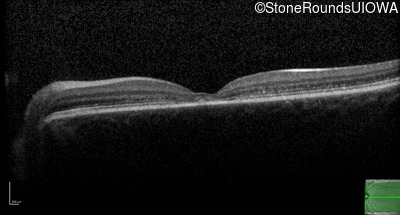

AR Stargardt Disease (IIA)

Age at visit:

14 years

OD

OS

20/32

20/20 -2

OCT Stack

AR Stargardt Disease

ABCA4

Gly607Arg GGG>AGG

Gly1961Glu GGA>GAA

AR